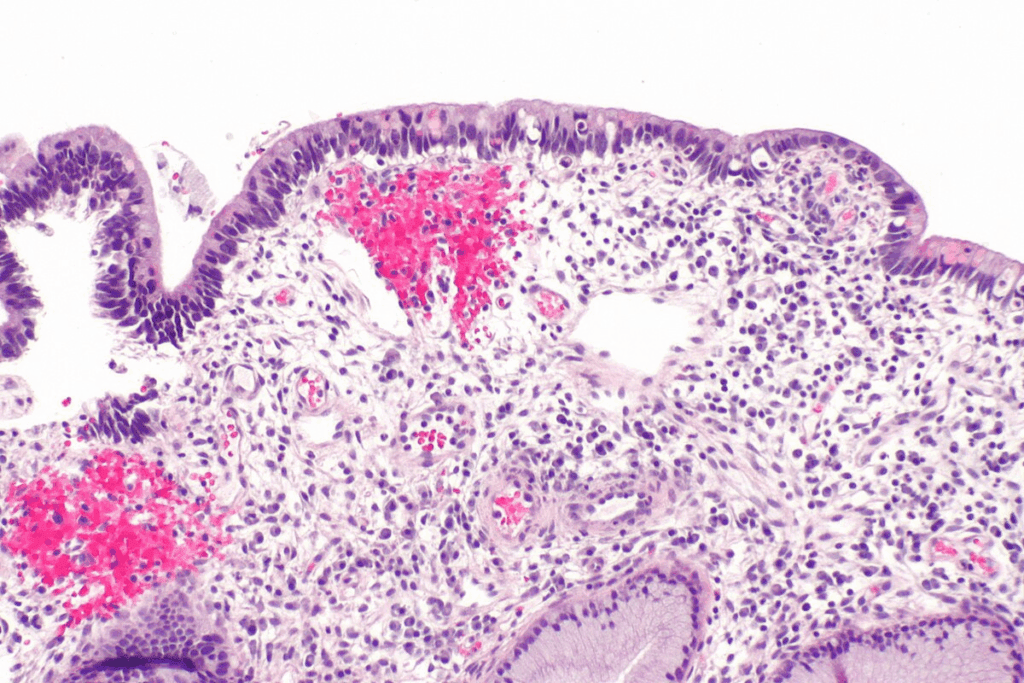

CIS cells have odd cellular and molecular traits, like invasive cancer cells. They show irregular cell shape, changed gene activity, and odd cell behavior. Yet, CIS cells stay in the epithelial layer.

CIS cells staying in the epithelial layer is key. It stops them from reaching blood vessels and lymphatic paths, lowering metastasis risk. This is vital for CIS prognosis and treatment.

When screening tests show CIS, biopsy techniques are used to confirm it. A biopsy takes a small tissue sample from the area in question.

The biopsy sample is then checked under a microscope in pathological assessment. This step is key to confirming CIS and ruling out invasive cancer.